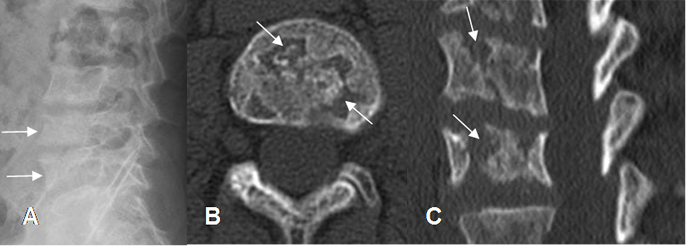

Fig 46. Anemia drepanocítica.

A: Rx lateral. Pérdida en la nitidez de los contornos de L4 y L5.

B: TAC axial y C: TAC reconstrucción sagital. Fragmentación de los cuerpos

vertebrales y defectos óseos por la presencia de infartos.